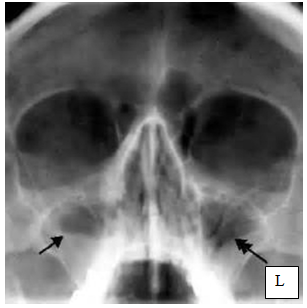

4.Назовите снимок, опишите  изменения, указанные стрелочками.

4. !!!!!!название: рентгенограмма околоносовых пазух в полуаксиальной проекции –

Изменена пневмотизация в/ч пазух(видим гомогенное затемнение), медиальные стенки пазух - пристеночная деструкция